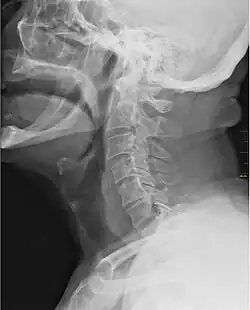

![]() X-ray showing the throat, seen as a dark band to the front of the spine | |

In vertebrate anatomy, the throat is the front part of the neck, internally positioned in front of the vertebrae. It contains the pharynx and larynx. An important section of it is the epiglottis, separating the esophagus from the trachea (windpipe), preventing food and drinks being inhaled into the lungs. The throat contains various blood vessels, pharyngeal muscles, the nasopharyngeal tonsil, the tonsils, the palatine uvula, the trachea, the esophagus, and the vocal cords.[1][2] The throat is supported by structures such as the hyoid bone and cartilage of the larynx.

It works with the mouth, ears and nose, as well as a number of other parts of the body. Its pharynx is connected to the mouth, allowing speech to occur, and food and liquid to pass down the throat. It is joined to the nose by the nasopharynx at the top of the throat, and to the ear by its Eustachian tube.[3] The throat's trachea carries inhaled air to the bronchi of the lungs. The esophagus carries food through the throat to the stomach.[4] Adenoids and tonsils help prevent infection and are composed of lymph tissue. The larynx contains vocal cords, the epiglottis (preventing food/liquid inhalation), and an area known as the subglottic larynx, in children it is the narrowest section of the upper part of the throat.[5][6]